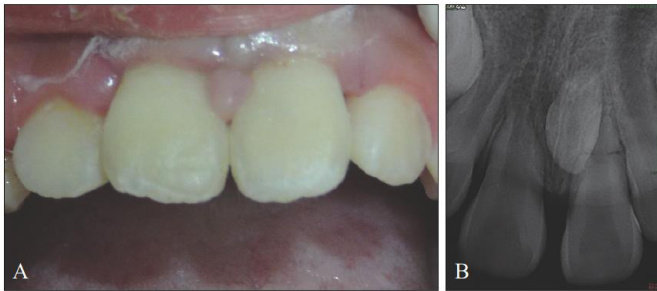

[中图分类号] R781.05 [文献标志码] A [doi] 10.7518/hxkq.2025.2025305 [摘要]前牙树脂充填修复技术因具有微创、美学效果佳等优势,广泛应用于临床诊疗。其短期疗效显著,但长期可发生修复体断裂、颜色变化等并发症,长期预后面临挑战。材料的选择、临床操作技术及患者相关因素均会影响修复的长期疗效。本研究对前牙树脂充填修复的长期预后进行分析,深入探讨影响其长期疗效